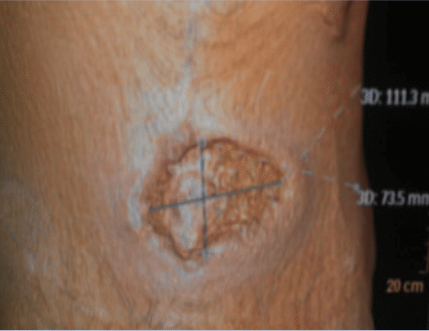

On the second postoperative day the patient’s blood pressure and pulse remained the same, but his temperature increased to 38.6°C. Inflammatory parameters including white blood count (34.5*103/mm3) and C-reactive protein (297.3 mg/L) were elevated. Blood cultures were negative. The patient was diagnosed with PG (Figures 1 and 2). After dermatological consultation, prednisolone (80 mg/day) was started, and azathioprine 150 mg/day was added 2 weeks later.

Figure 1. The appearance of the lesion upon admission, 1week after drainage of the abscess.